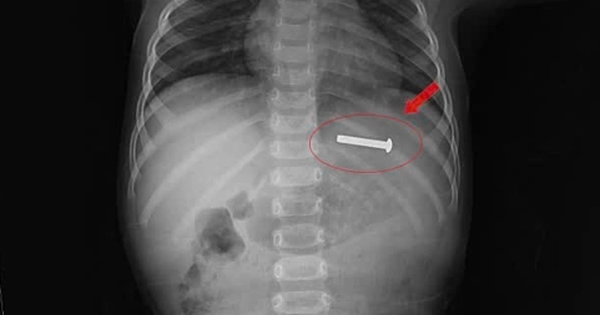

Gắp chiếc đinh vít dài 5 cm từ dạ dày trẻ 15 tháng tuổi